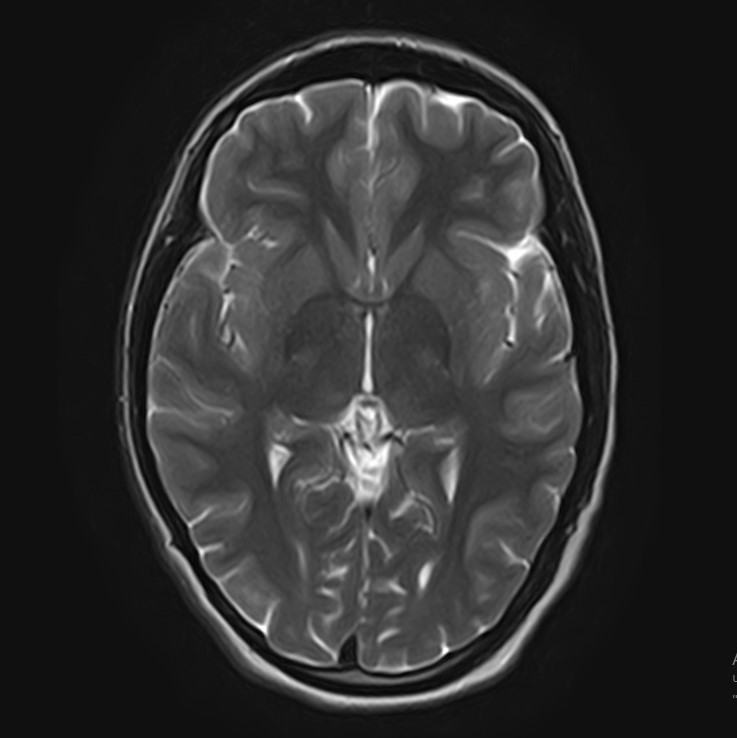

3. При головной боли, надо обязательно сделать МРТ

Действительно, зачастую приходят на МРТ пациенты, страдающие головной болью. Однако, в подавляющих случаях, МРТ не дает каких-то неблагоприятных результатов. Такая головная боль, как правило, связана с психоэмоциональными или психофизиологическими особенностями как организма, так и образа жизни (стресс, переутомление, несоблюдение режима труда и отдыха и т.д.). Но стоит отметить, что проведение МРТ даст дополнительную информацию Вам о состояние головного мозга и тем самым “успокоит” Вас.